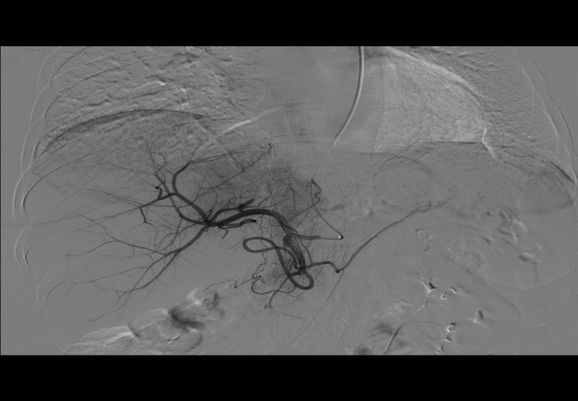

DSA(一)

检查时间:2018年10月22日

影像图谱:

肝总动脉造影见左肝及部分右肝投影区见大片状异常染色。